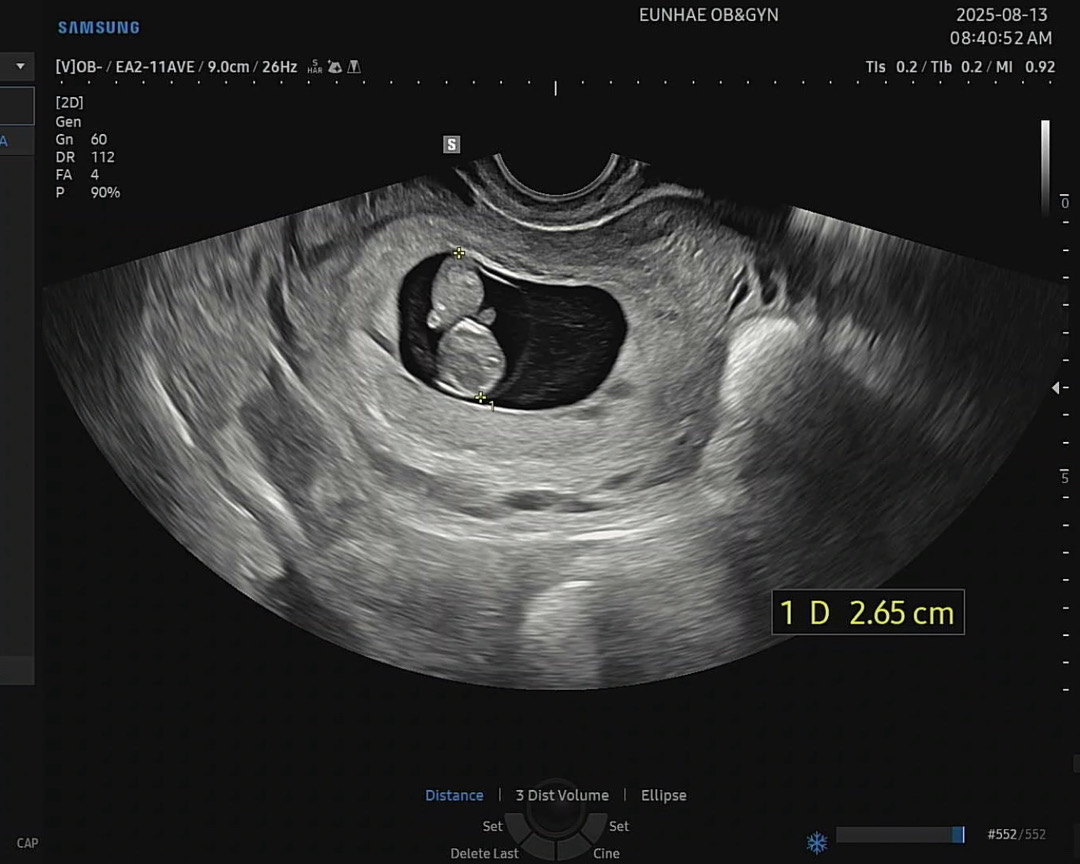

안녕하세요! 9주차4일 되고 며칠전 초음파를 보고왔습니다. 12주차에 기형아검사를 이제 한다고 하시던데 다른분들은 정밀초음파(입체초음파인가요?) 를 하시는분들이 있더라구요. 여쭤보니 정밀초음파는 20주때 한다고 하셔서 일반 초음파실에서 좀더 오래 기형아검사를 한다고 말씀주신 것 같아요. 혹시 정밀초음파로 입체로 보는것은 12주차에 안하는 안하신분들도 많으실까요?

12주차에는 1차 기형아검사로 보통 목투명대 재는 초음파만 봅니당~ 나이가 많거나 뭔가 이상소견이 나오면 니프티나 양수검사 같은 선택지도 있어요 정밀초음파는 20주 지나서 2차검사때 해요! 아기 장기와 손가락 발가락 하나씩 다 검사해요 ㅎㅎ